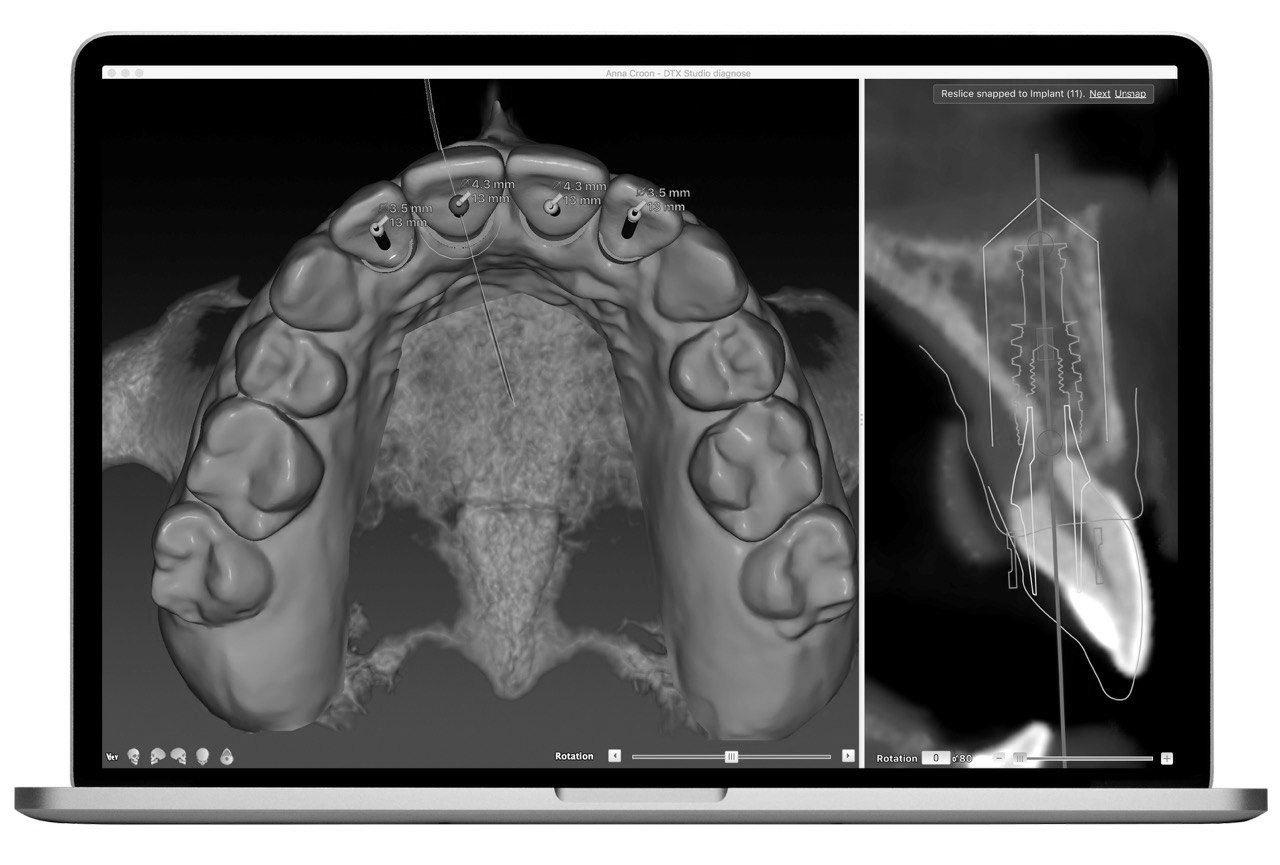

Мы устанавливаем импланты по предварительно изготовленному хирургическому шаблону, благодаря чему установка их происходит точно в том положении как и было запланировано врачом до операции. Это значительно сокращает время процедуры, а также делает конструкцию максимально надежной и эстетичной.